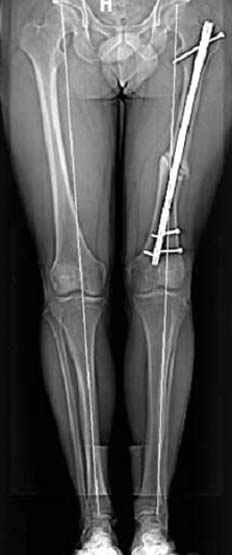

пластическая модель; и коррекция бедра аппаратом Илизарова.

Имею другие снимки тоже, получится как отчет о моей работе.

С уважением Джолдас